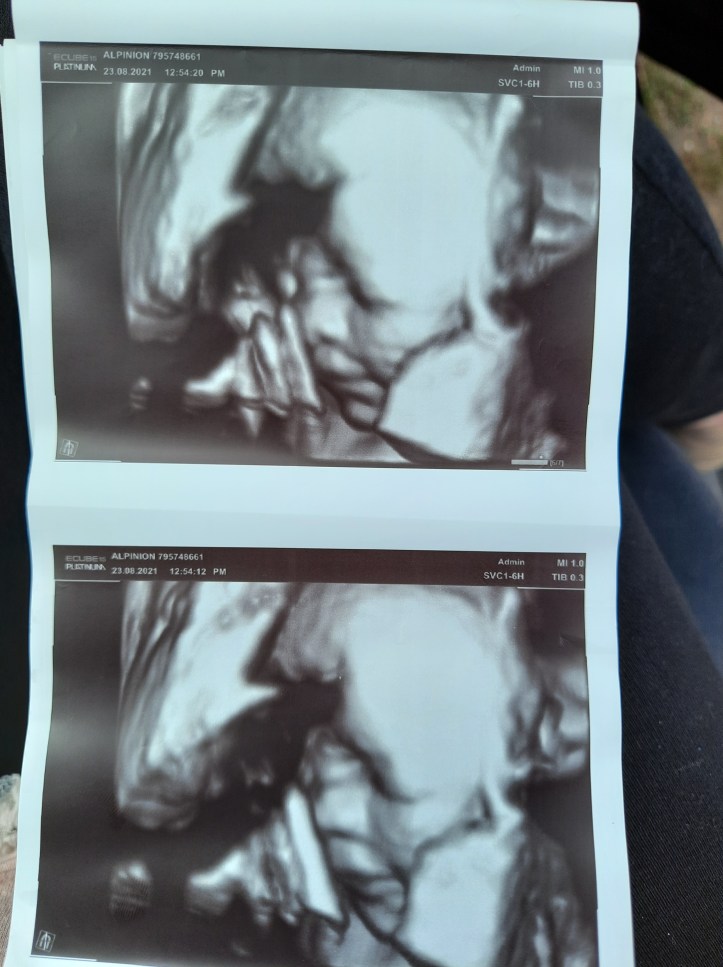

Musze Wam kogoś przedstawić. Oto owoc naszej 8,5 letniej walki, miłości, determinacji i nadziei. Choć wciąż trudno jest mi w to uwierzyć, udało nam się odczarować ciążooporność. Za kilka tygodni świat pozna prawdziwy CUD, który dziarsko funduje matce crossfit połączony z pilatesem a pęcherz zaadaptował na worek treningowy. Oto nasza córka, która dzięki pomocy medycyny od 26 lutego 2021 roku rośnie pod moim sercem.

Ciąża to dla mnie spore zaskoczenie, mimo że była ona zaplanowana do granic możliwości ze względu na in-vitro. Znaliśmy bowiem dokładną datę transferu zarodka. Jest to wciąż abstrakcyjny stan. Bez dwóch zdań mogę powiedzieć, że to stan błogosławiony. Mimo cukrzycy ciążowej i setek zastrzyków z heparyny jakie muszę przyjmować codziennie nie mam absolutnie powodów do narzekania.

pozdrawiamy Was w 32 tygodniu ciąży

Emilia z mężem oraz Mańkowa (tymczasowe imię naszej córki)